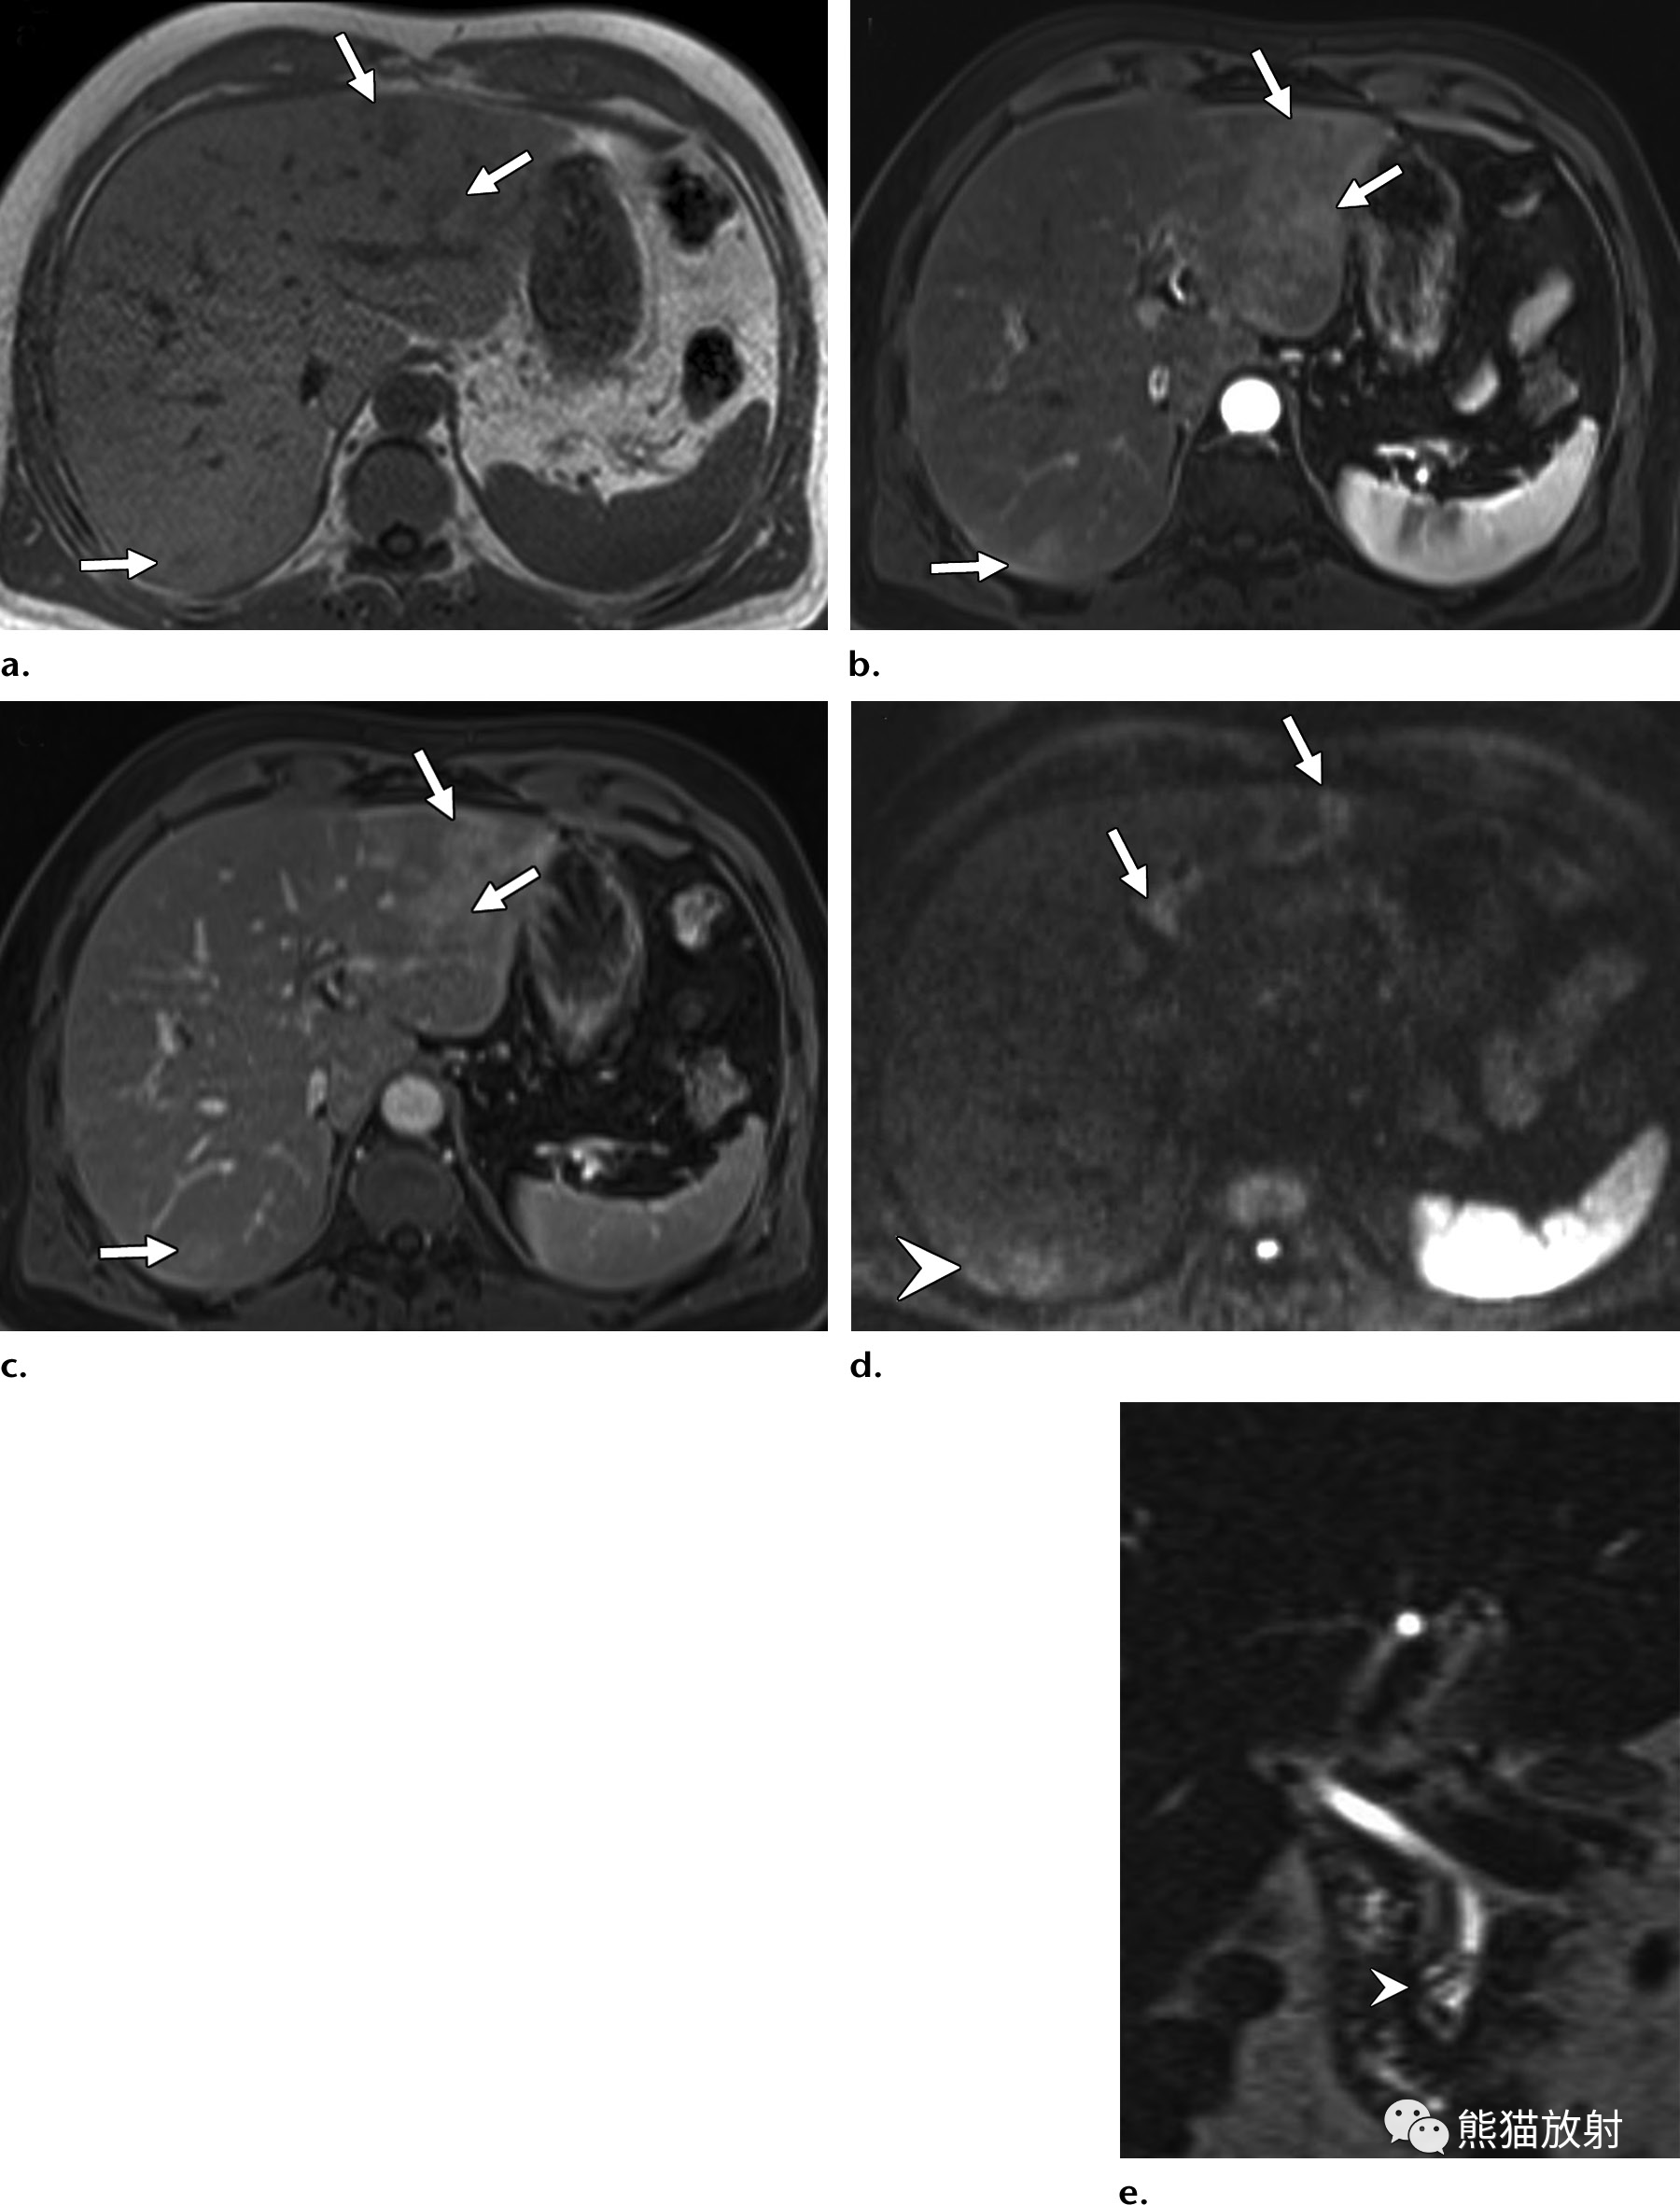

b16de3fa39adcd79537123cadf8f3c03.png 32岁 HIV/AIDS男性患者,细菌性紫癜,表现为发热。

(a)T1WI同相位图像显示肝右叶后段边界不清的等至轻度低信号结节(箭)。(b)脂肪饱和T2WI显示结节呈中高信号(箭),后方肝被膜下见数个较小结节(箭头)。(c)增强动脉早期图像显示结节周围不规则明显强化。(d)增强延迟期结节内部延迟强化,由于造影剂滞留在病灶内扩张的肝窦内,因此达到与周围肝静脉结构相似的信号强度。